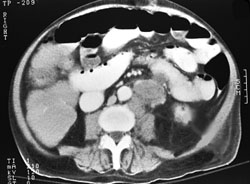

Colon cancer ct scan. Ct scans use radiation x rays to form images while colonoscopy uses a flexible instrument equipped with a light and camera to form images. Treatment for colon cancer usually involves surgery to remove the cancer. This test can help tell if colorectal cancer has spread to nearby lymph nodes or to your liver lungs or other organs.

A ct scan uses x rays to make detailed cross sectional images of your body. Benefits of a colon ct scan over other investigative methods include its ease of use and the fact that sedation is not necessary. Ct scans utilize x rays to form images of organs and tissues inside the body for example abdominal organs brain chest lungs heart while colonoscopy is a procedure that can visualize only the inside surface of the colon.

Are you preparing to have this procedure soon. A pelvic ct scan can be used to detect several types of cancer. Its purpose is to provide digital images of the inside of the colon and document the size and location of abnormalities.